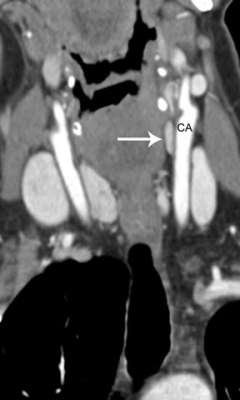

How do imaging results (scans) influence eligibility for re-do parathyroid surgery? The importance of parathyroid 4-D CT.

To a significant degree, re-do parathyroid surgery is driven by the presence of a clear anatomic target. Since 2012, UCLA Endocrine Surgery has employed parathyroid 4-D CT in the planning of all reoperations for primary hyperparathyroidism. [see video on parathyroid 4-D CT]. 4D-CT provides the highest possible anatomic detail and affords the highest likelihood of achieving a safe and successful second operation.

For us, 4D-CT technology has been a "game changer," enabling >95% of patients with failed initial operations to become eligible for reoperation, greatly aiding our ability to counsel patients on surgical strategy, and allowing us to complete reoperations in a much shorter time. Many patients are understandably disappointed and wary after their first parathyroid operation has failed. 4D-CT allows us to sit down with the patient and walk through a series of high-resolution images so that the patient and their family can get a clear understanding of the surgical plan.